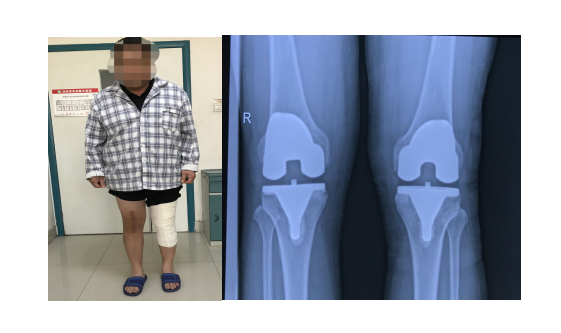

聊城市中医医院国医楼骨关节科门诊里,东昌府区朱老庄镇的张大爷,紧紧地握着刘刚主任的手说:“感谢刘主任和关节科各位大夫护士,把我的两个膝盖治好了,不光治好了我多年的罗圈腿,腿变直了,更没想到的是,两次手术以后,我竟然没怎么疼,早知道这样,我早几年就来了,就是害怕,白白在家受了这几年罪啊,今天我出院了,专门来感谢你们!”。这是出现在我院骨关节科里医患互动的一幅感人画面,也是骨关节科将快速康复理念应用于髋膝关节置换患者管理后取得良好效果的真实印证!

我院骨关节科自2016年率先将加速康复理念(ERAS)应用于髋膝关节置换患者围手术期的管理当中。我院于2021年被国家卫健委纳入加速康复外科第二批骨科试点医院。骨关节科在工作实践中结合中医药优势,创新思路、拓宽渠道,不断总结完善提高,目前已形成特色突出的髋膝关节置换快速康复流程,为广大关节置换患者带来了福音。 将加速康复外科理念融入到髋膝关节置换患者的康复过程中,能有效降低患者术后疼痛、血栓、感染、贫血等并发症和不良反应发生率,使患者手术后无痛、无应激反应,提高患者康复过程的舒适度,加速患者康复,提高临床疗效。 为此我院骨关节科专门制定了具有中医特色的髋膝关节快速康复流程及患者康复指导宣传手册。设定了髋膝关节置换快速康复“十无”目标:无痛、无血栓、无出血、无感染、无肿胀、无引流管及尿管、无止血带、无呕吐、无应激、无风险。 对每一台关节置换手术,骨关节科都要进行晨间术前讨论,针对患者适应症的选择是否合适,有无需要治疗的内科疾病,预计手术操作中会遇到的问题和需要注意的要点,进行详细的讨论,做好周密的手术规划,为手术的成功奠定基础。 骨关节科针对每一例髋膝关节手术患者,在病人入院起,即进入康复流程。 术前对患者进行疼痛及关节功能评分,指导患者术前学习功能锻炼方式,口服止痛药物超前镇痛,术中关节周围软组织封闭、术后给以静脉及口服止痛药物、镇痛药微量泵、耳穴压豆、外用冷疗等多模式镇痛措施。术后给于口服三七粉活血止血,指导患者行踝泵及股四头肌功能锻炼、行下肢足底泵治疗预防血栓,腹部灸疗及穴位贴敷缓解术后胃肠道反应,等等一系列具有中医特色的快速康复治疗措施。 骨关节科行髋膝关节置换患者,术后第一天即在主管医师的指导下,下地行功能锻炼。主管医师每天都要对患者进行功能锻炼的指导和沟通,针对患者康复过程中遇到的问题,给与耐心细致的讲解,缓解患者心理压力,鼓励患者积极康复锻炼。 百舸争流,奋楫者先;千帆竟发,勇进者胜。骨关节科坚持定期开展髋膝关节置换相关知识的集中学习,通过学习国内知名专家的讲座,查找问题,总结经验,不断提升理论技术水平。骨关节科每周六晨间交班后,都要进行关节置换术后影像点评,总结经验,在不断探索中创新,在反复实践中提升,通过多种形式的学习、交流,使骨关节科手术理念、手术方式都紧跟学术前沿,努力追求打造髋膝关节置换快速康复流程“十化”,即规范化、标准化、精准化、数字化、个性化、微创化、透明化、流程化、差异化、智能化。 骨关节科全体医护人员将本着精益求精的专业精神,坚持以病人为中心的服务理念,为每一位髋膝关节置换患者提供安全、优质的医疗服务,使患者安全、舒适地度过围手术期和功能康复期,使病人快速康复,优质康复,让病人在治疗康复过程中感到舒适和满意! 骨关节科:聊城市中医医院国医楼六楼 电话:8341447/8341448 供稿|刘晓之(骨关节科)